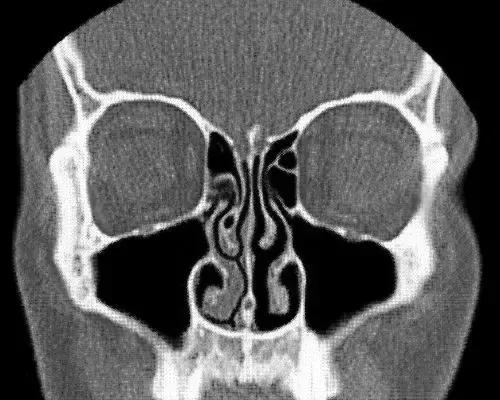

CT扫描下显示的鼻周期证据,左侧鼻甲充血肿胀,而右侧则畅通无阻

这与病理性的鼻塞是不同的。

所以我们在日常生活中,并不能感知到这种鼻周期的存在。